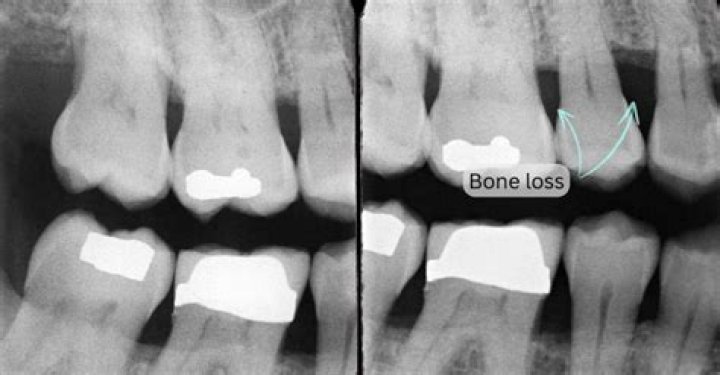

Can you see bone loss on an X-ray? However, x-rays are note used to diagnose osteoporosis. X-rays can only detect bone loss after 25-40 percent of the ske...